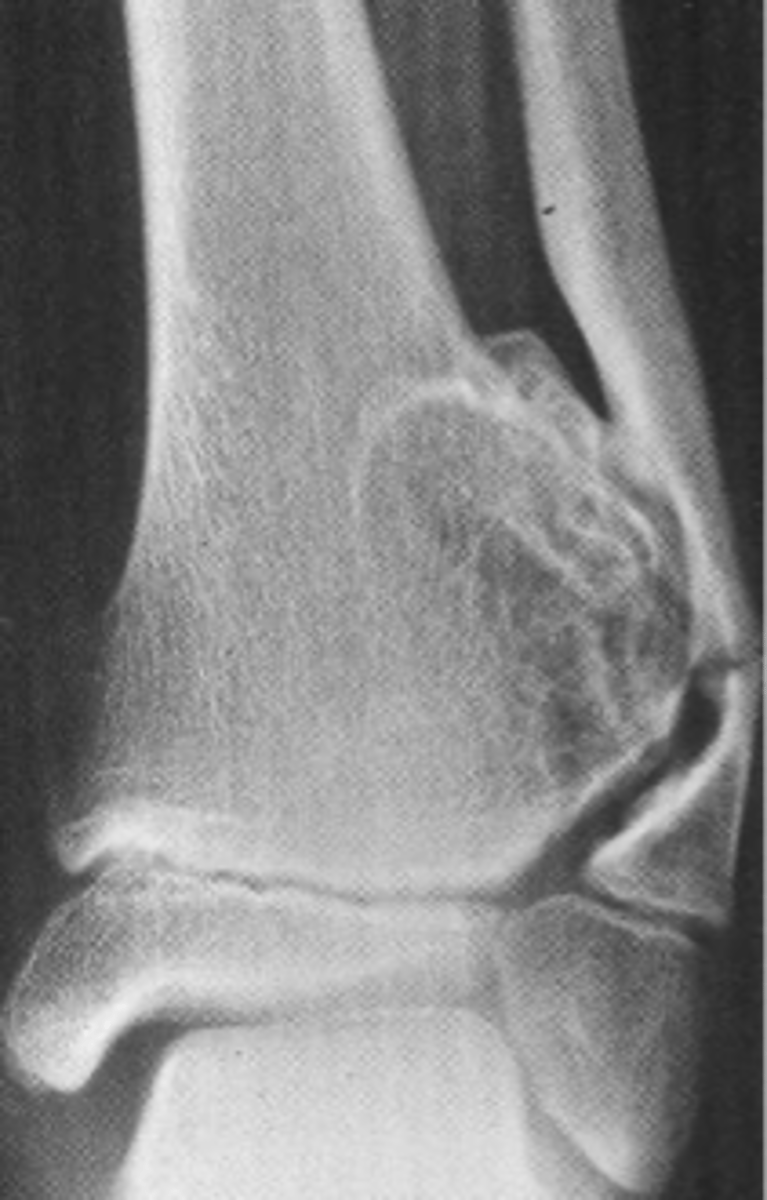

Aneurysmal bone cyst

- 1% of biopsied primary bone tumors

- M:F, 2:3

- 5-20 y.o.

- Acute pain

- Previous trauma

- 80% tubular bones and spine

<p>- 1% of biopsied primary bone tumors</p><p>- M:F, 2:3</p><p>- 5-20 y.o.</p><p>- Acute pain</p><p>- Previous trauma</p><p>- 80% tubular bones and spine</p>

- Eccentric

- Metaphyseal

- Osteolytic with fine trabeculae

- Saccular ballooning of cortex

- May cross epiphysis

- Periosteal buttressing

State the radiographic features of aneurysmal bone cyst in tubular bones

<p>State the radiographic features of aneurysmal bone cyst in tubular bones</p>